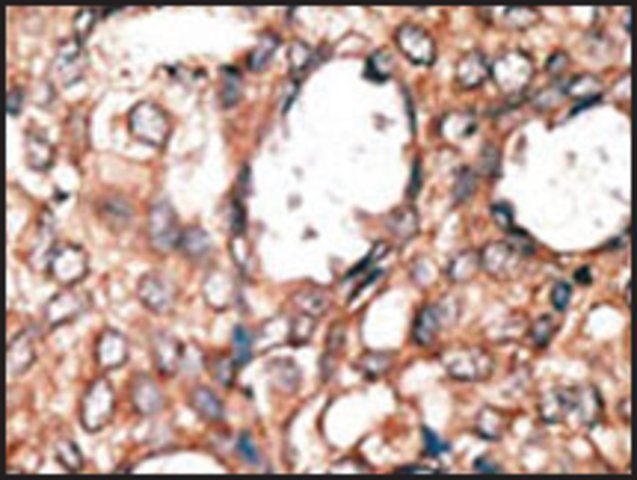

Anti-MKL1 polyclonal antibody is used to tag megakaryoblastic leukemia-1 for detection and quantitation by Western blotting and in plasma by immunohistochemical (IHC) techniques. It is used as a probe to determine the roles of megakaryoblastic leukemia-1 in the Rho/megakaryoblastic leukemia 1 (MKL1) signaling pathway and a variety of cell processes such as cell mobilization and the epithelial-mesenchymal transition (EMT).